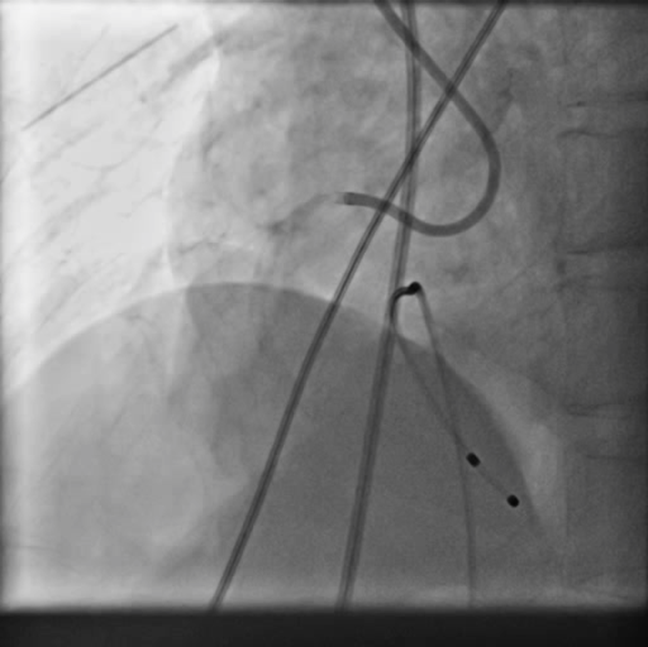

•Thisa case of 72 years male who presented to us with inferior wall STEMI, completeheart block with delayed presentation in cardiogenic shock and severe LV dysfunction. Patientwas put on temporary pacing support, IABP support and coronary angiogram wasdone which revealed TVD with rightcoronary artery had near total occlusion with extensive calcification alongwithsignificant calcified stenosis in left system. Heart team meeting done urgently and planned to go for high risk PCI.

patient underwent coronary angiogram which revealed calcified triple vessel disease with near total occlusion of proximal RCA and 80% calcified stenosis in mid LAD with diseased small circumflex artery. In view of very high surgical risk he was turned down by surgical team and was advised for a high risk PCI of infarct related artery on hemodynamic support in form of IABP which was only mechanical circulatory support available apart from VA-ECMO.

PCIof right coronary artery was initiated on IABP support with amplatz left1 guided catheter and vessel was crossed with great difficulty in repeatedattempts by fielder XT followed by GAIA 2 wire over corsair microcatheter. Microcathetercould not be crossed beyond mid segment calcified CTO, so balloon dilation with0.75 mm balloon was done after which again microcatheter could not be trackedbeyond mid part. Butwe were able to exchange wire to allstar followed by rotawire byplacing microcatheter in mid segment after balloon dilation by 0.75 mm balloon. Rotablation wasdone with 1.25 mm burr at 1,60,00 rpm repeatedly from proximal to mid distalpart. Lesionstill looked unprepared as repeated postdilation with2.25*15 mm followed by 2.5*15 mm non compliant balloon at high pressures showedunexpanded balloon. Againlesion preparation was done with 2.5*15 mm wolverine cutting balloon repeatedlyat high pressures which led to adequate luminal gain and calcium cracks as seenon IVUS run. AfterIVUS run again high pressure balloon dilation was done with wolverine 2.5*15 mmballoon followed by 2.5*12 mm non compliant balloon at 28 atm toadequately prepare the lesion before stent deployment. Stentingwas done with 2.5*32 mm DES, 2.75*32 mm DES, and 3*24 mm DES from distal toproximal in overlapping fashion. Thenfinally high pressure post dilation was done with 2.75*15 mm followed by 3*15mm non compliant balloon and adequate stent expansion was achieved with TIMI 3 flow.